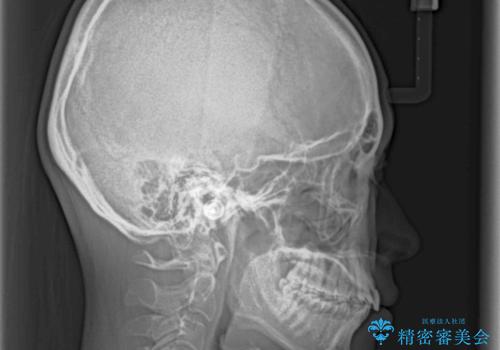

上顎の歯列全体が、下顎歯列に対して前方に位置しており、その影響で上顎前歯がやや前方に突出している状態でした。

横顔の印象から、抜歯をして積極的に口元を引っ込める必要はなかったため、アンカースクリューを用いて上顎歯列全体を後方に移動させることとしました。